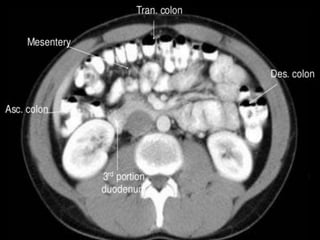

Small Bowel.

Central position

in the abdomen

Valvulae

conniventes -

mucosal folds

that cross the

full width of the

bowel

(arrowheads)

• Colon has sacculations

called haustra as teniae coli

are shorter than the colonic

wall

• Colon is relatively peripheral

SoftTissue Structures: Subtle on

KUB.

Right common iliac

vein.

CT cross sectional

anatomy.